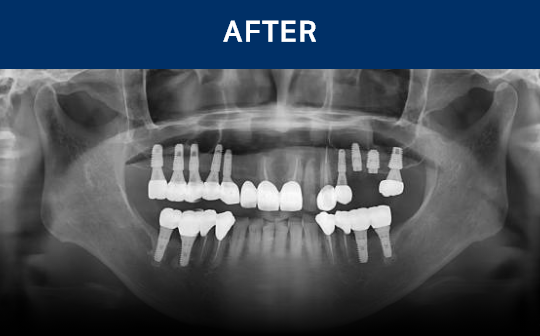

전후가 명확한 결과, 그 결과가

곧 신길플란트치과의 신뢰입니다.

불편함 없이 웃고, 걱정 없이 드실 수 있도록 임플란트로 일상의 편안함을 되찾아드리겠습니다.